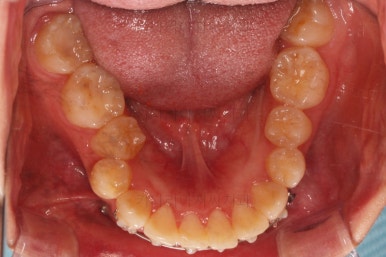

교합, 과개교합 모두 좋아졌고요.

발치 공간도 깔끔하게 닫히고 종료했습니다.

이제 부산무턱교정치과 전후 비교해 볼게요.

웃을 때 튀어나와 보이던 앞니도 많이 개선디ㅗ었고, 치열도 매우 예뻐졌습니다.